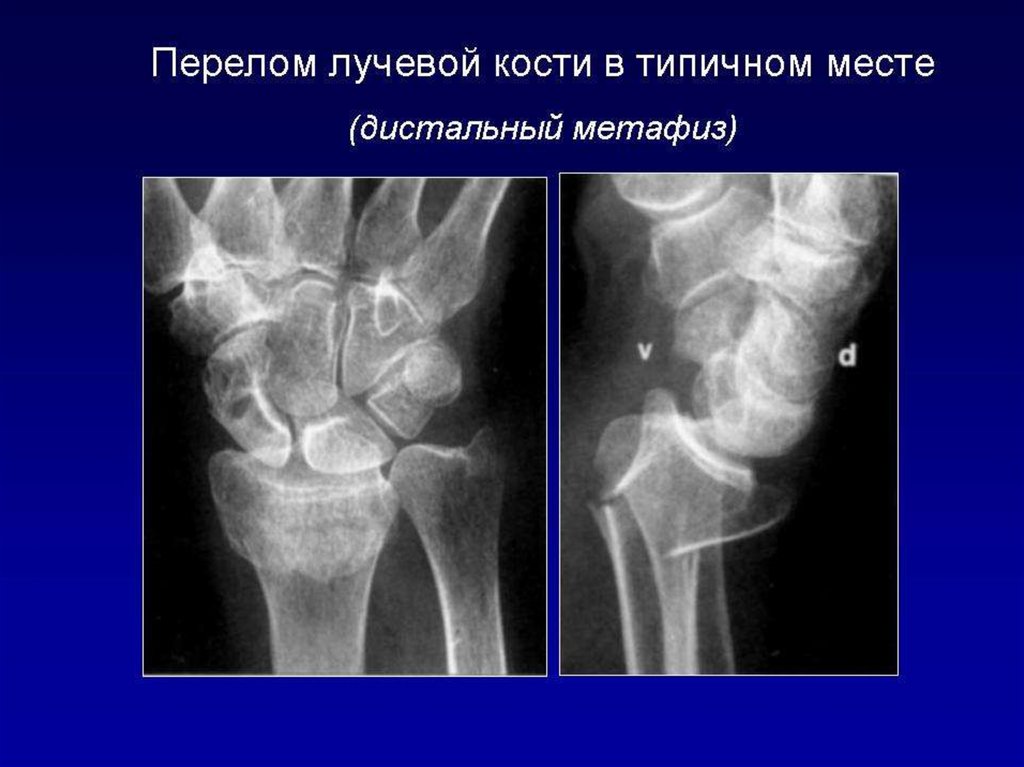

Лучевое исследование костно-суставной системы. Методы исследования. Семиотика